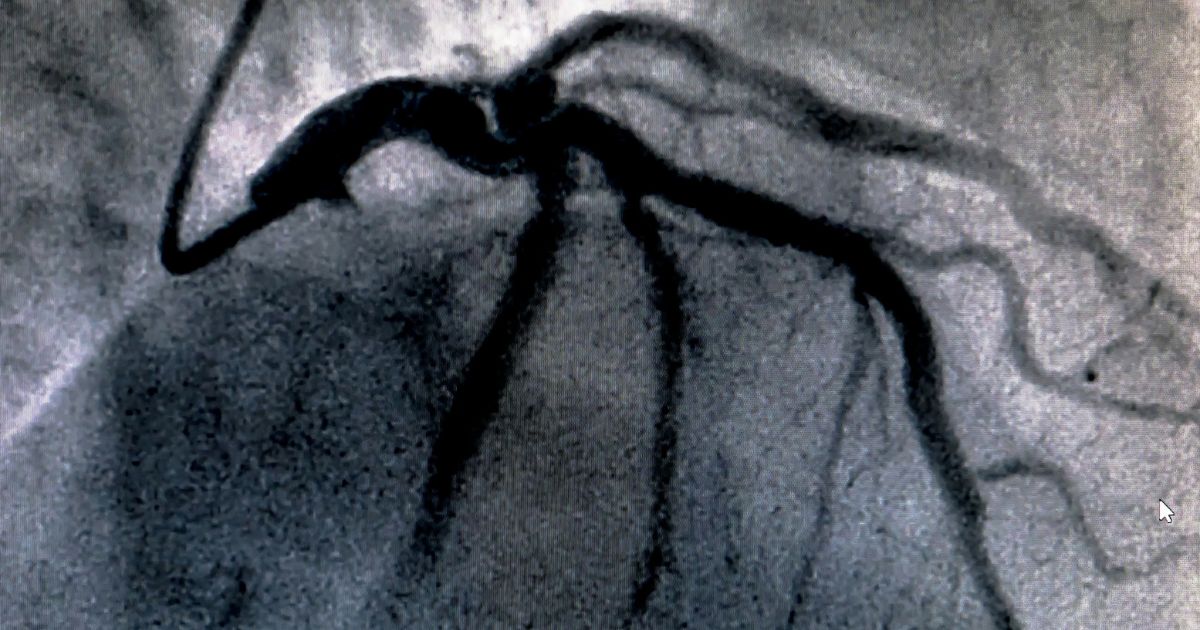

Η κοιλιογραφία συνήθως πραγματοποιείται παράλληλα με τη διενέργεια στεφανιογραφίας, με την τοποθέτηση ενός λεπτού καθετήρα στην αριστερή κοιλία, που γίνεται για τη διάγνωση συγκεκριμένων καρδιακών νοσημάτων. Ο καθετήρας τοποθετείται στην αριστερή κοιλία διαμέσου της αορτικής βαλβίδας.

Μετά χορηγείται σκιαγραφική ουσία στην αριστερή κοιλία και μελετάται η κινητικότητα των τοιχωμάτων καθώς και η στεγανότητα της σύγκλεισης των βαλβίδων. Είναι μια διαδικασία πολύ σημαντική στη διερεύνηση βαλβιδοπαθειών (στένωση ή ανεπάρκεια αορτικής βαλβίδας, ανεπάρκεια μιτροειδούς βαλβίδας), στην εκτίμηση της κινητικότητας των καρδιακών τοιχωμάτων καθώς και στην παρουσία μεσοκοιλιακής επικοινωνίας.